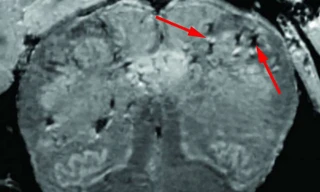

TPO - Một trong những dấu hiệu ban đầu của việc nhiễm SARS-CoV-2 là mất khứu giác và vị giác đột ngột. Thông thường, những triệu chứng này vẫn tồn tại rất lâu sau khi người nhiễm bệnh dường như đã khỏi. Làm thế nào virus SARS-CoV-2 có thể xâm nhập vào hệ thần kinh?